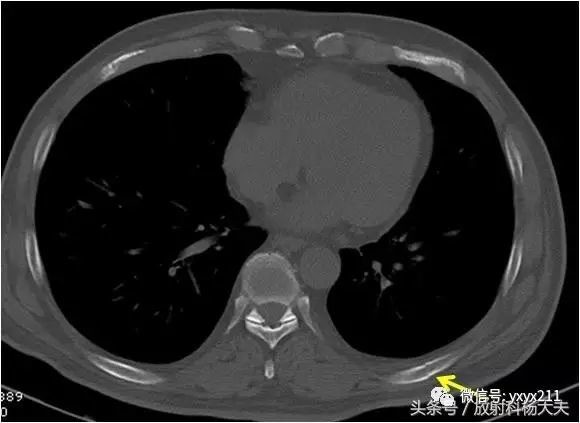

第 9 肋骨 骨折-肋骨の全体的な骨折では前述した通り第4肋骨~第8肋骨の骨折が多くなります。 しかし、ゴルフや野球のスイングなどによる疲労骨折のケースでは第4肋骨~第8肋骨だけでなく 第1肋骨 第2肋骨 の2箇所も疲労骨折を生じやすくなります。 一、第九根肋骨骨折是否严重 肋骨骨折容易并发以下的疾病,还是比较严重的: 1急性心力衰竭 肋骨骨折并发急性心力衰竭的病例多为多发性肋骨骨折,此病的患者早期应密切观察生命体征及病情变化,防止心肺功能衰竭,一旦出现早期症状应立即组织抢救,严防发生心跳骤停,心跳一旦停止不

症状: 休克 胸痛 无力 水肿 表现: 1、症状 偶尔由于剧烈的咳嗽 或喷嚏等,胸部肌肉突然强力收缩而引起肋骨骨折,称为自发性肋骨骨折,多发生在腋窝部的第6~9肋,当肋骨本身有病变时,如原发性肿瘤或转移瘤等,在很轻的外力或没有外力作用下亦可发生肋骨骨折,称为病理性肋骨骨折。我想问一下肋骨折了一根然后 如果肋骨折了插到肺里去会有生命危险吗? 本人今年51岁,四个月前上肋骨折接好后, 肋骨折后如何睡觉 ;